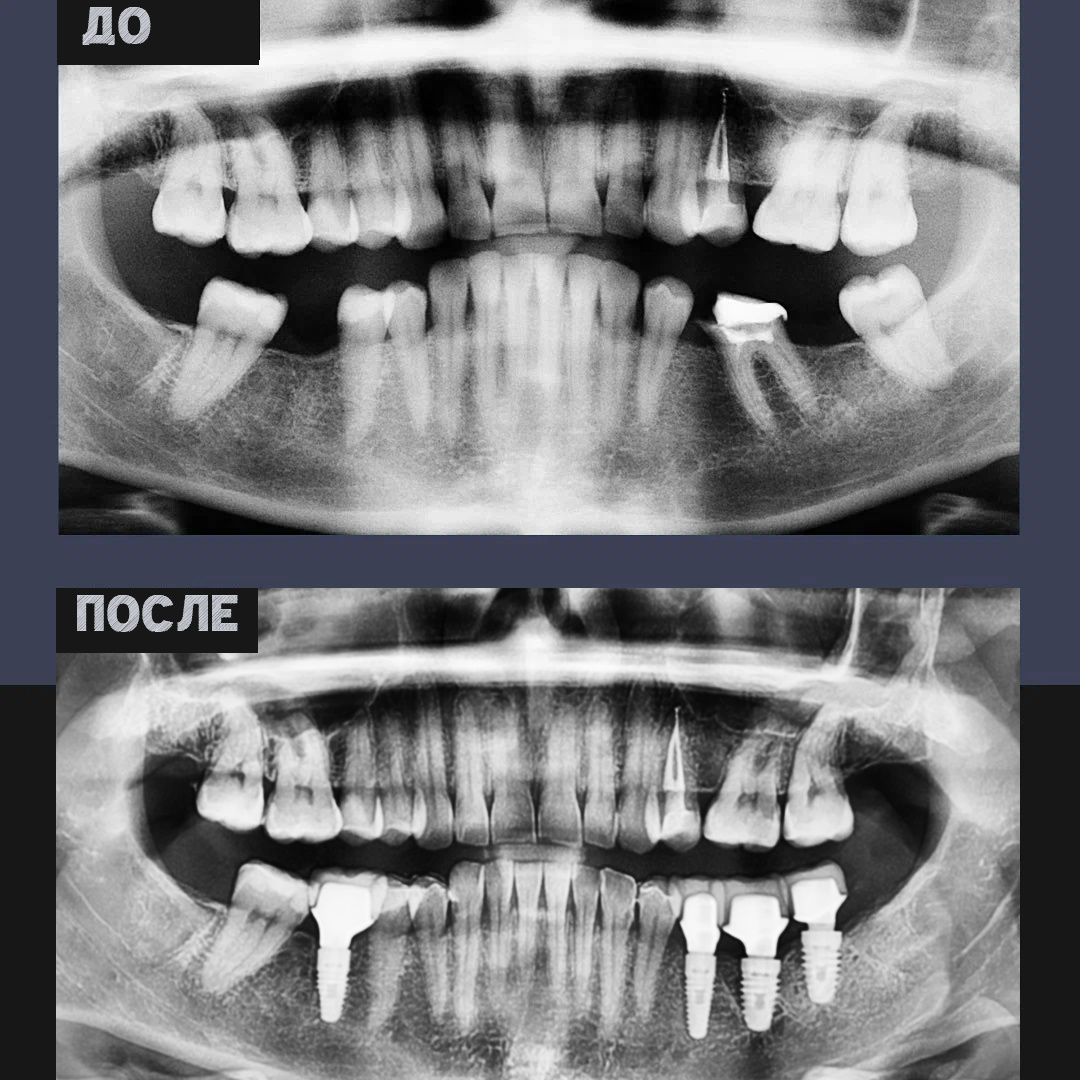

Пациентку принял челюстно-лицевой хирург Д.Н. Назарян. Проведя диагностику, он предложил комплексный подход, который позволил минимизировать травматичность и ускорить процесс восстановления.

🔹 Проведена операция на мягких тканях

🔹 Удалён несостоятельный зуб

🔹 Одномоментно установлено четыре импланта

Чтобы добиться максимальной точности и безопасности, имплантация была предварительно смоделирована в 3D-формате. Это позволило избежать ошибок в позиционировании имплантов, что важно для их долгосрочной стабильности.

После заживления главный врач NKclinic Г.Г. Кялов завершил лечение, установив постоянные коронки.

Результат: жевательная функция и естественная эстетика

🔹 Полностью восстановлены жевательные зубы

🔹 Улучшена эстетика улыбки

🔹 Исключён дискомфорт при приёме пищи